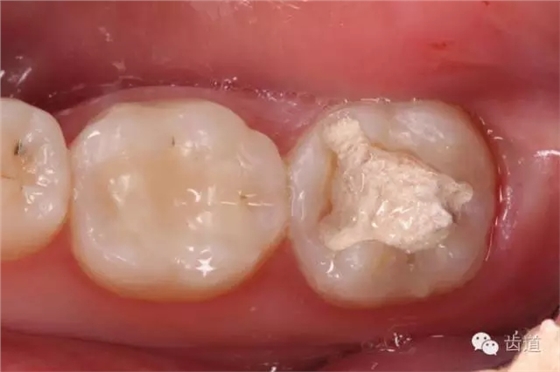

三診(2015.03.03): 主訴:復(fù)診,癥狀消失,無(wú)不適。 檢查:37暫封無(wú)缺損,探痛-,叩痛-,松動(dòng)-,牙齦無(wú)紅腫。 治療過(guò)程:37去盡暫封及原充填物,去盡無(wú)基釉,制備嵌體洞型,流動(dòng)樹(shù)脂完成即可牙本質(zhì)封閉,鎢鋼真拋光釉質(zhì)邊緣,利用硅橡膠印模材料制取印模,ZOE暫封洞形。

2. 去盡暫封及原充填物,發(fā)現(xiàn)近中頰側(cè)壁較薄,有無(wú)基釉殘余

3. 制備嵌體洞型,去盡無(wú)基釉

4. 精細(xì)修整洞型